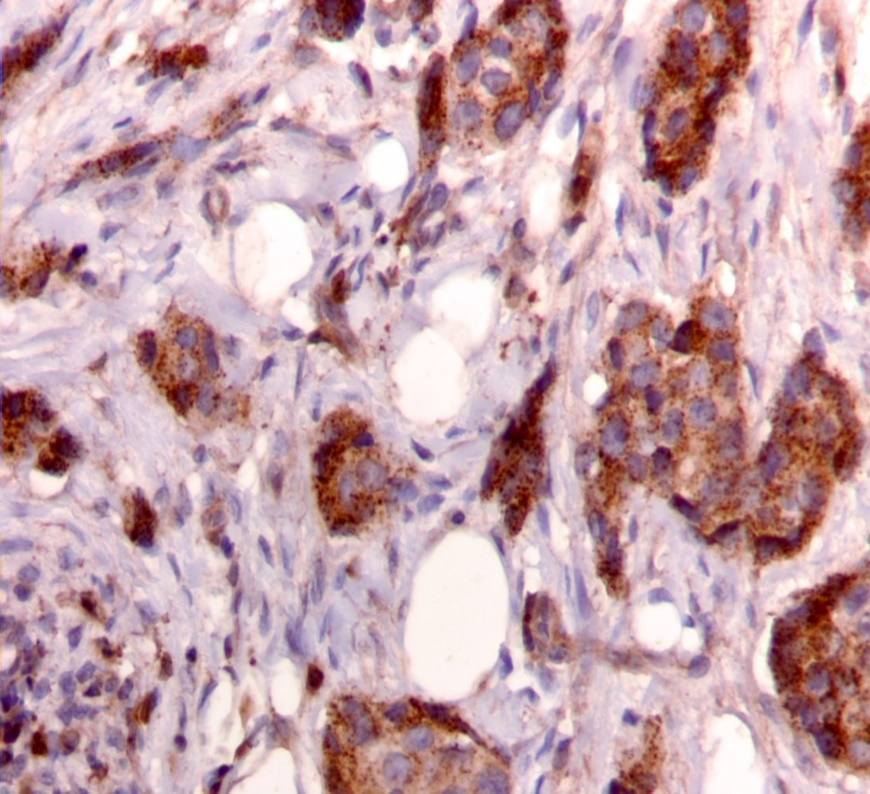

Figure 2.Diffuse cytoplasmic staining pattern for IRS-2. (IRS-2 immunohistochemical stain, 200x magnification)

We used the following histologic criteria for IRS-1 and IRS-2 staining patterns which are outlined in a previous study.13 For IRS-1, a nuclear pattern was defined as diffuse nuclear staining (Figure 1). IRS-2 staining patterns were defined using the following criteria: Diffuse cytoplasmic staining was defined as evenly distributed cytoplasmic reactivity (Figure 2); punctate cytoplasmic staining was defined as clearly demarcated puncta of staining within the cytoplasm (Figure 3); and membrane staining was defined as focal or diffuse membranous staining (Figure 4). Sections of normal pancreas and normal breast tissue were used for positive and negative controls. The pathologists assessing staining patterns were blinded to the tumor recurrence score and all other data at the time of assessment.